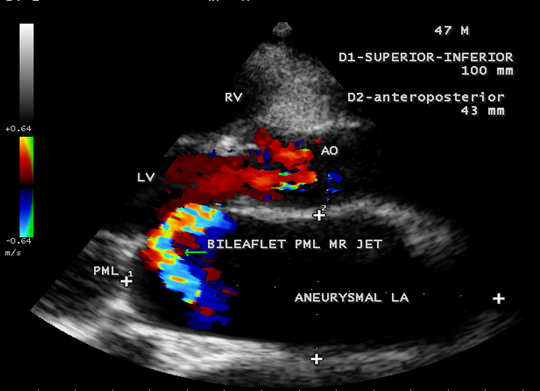

Case 2. PML (posterior mitral leaflet) prolapse causing severe mitral regurgitation with aneurysmal LA (left atrium) as shown in Figures 3 to 8 due to PML chordal rupture of rheumatic etiology in a 47- year old male. Patient was advised lifelong penicillin prophylaxis and MVR (mitral valve replacement).

Figure 5. Parasternal long axis view showing the ‘bileaflet’ MR (mitral regurgitation) jet originating from PML (posterior mitral leaflet) in a 47-year-old male.

Figure 6. Parasternal long axis view showing the ‘bileaflet’ mitral regurgitation due to PML chordal rupture in a 47- year old male.